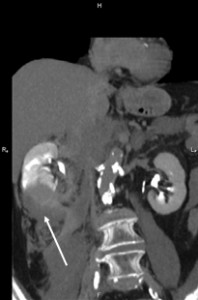

The patient was under observation on the cathlab floor during the next 60 minutes and after that the sheath was removed and hemostasis was achieved. She returned to her room but no longer then 15 minutes after she reported nausea, diaphoresis and weakness. Hypoglycemia was initially suspected but the glucotest showed a 260 mg/dl value of the serum glucose. The patient became hypotensive (systolic blood pressure 80 mm Hg) and soon after she complained of increasing pain in the right lumbar area. An ultrasound made at the bedside showed a right perirenal hematoma. The lab test indicated a dramatic decrease in the hemoglobin level, from 13 mg/dl to 8.0 mg /dl. The patient was practically in hemorrhagic shock. The decision was to transfer immediately the patient to the cathlab for an angiographic control. A new puncture of the right femoral artery was made, because the initial suspicion was an iliac rupture or perforation in the stent area, due to the extensive calcification of the arterial wall. The first injection of contrast media through the sheath showed that there was no problem with the stent. After that a global injection into the abdominal aorta, at the renal arteries level, was made, and a small effraction in the right renal parenchyma was observed (Figure 3). Selective intubation of the right renal artery was made with a JR 4.0 diagnostic catheter and that confirmed the source of bleeding in the right posterior segmental artery (Figure 4). Careful superselective intubation of this branch was performed (Figure 5), and small particles of gelatin sponge (Gelaspon) mixed with contrast media were delivered through the catheter. The embolization7 was successful in stopping the bleeding (Figure 6) but since there was about 20% of the renal parenchyma without vascularization and the patient still had important pain in the lumbar area, the decision was to transfer her to the urology department. A CT-scan (Figure 7) indicated a large subcapsular and retroperitoneal hematoma and also the presence of the contrast media in the urinary tract, an indication that the renal function was still preserved. In accordance with these findings, a renal lobectomy (partial nephrectomy) was performed, along with the evacuation of the hematoma. There was a parenchymal sparing intervention that preserved almost the entire kidney. The outcome was complicated by a pneumothorax after a central venous catheter insertion and by a right femoral hematoma following the two arterial punctures. However, after 14 days the patient was discharged in pretty good condition. One year later she has no claudication, the pulse in the right femoral artery is very good and the serum creatinine is normal.

Figure 5. Superselective intubation of the “guilty” segmental artery; arrow indicates the large subcapsular hematoma.